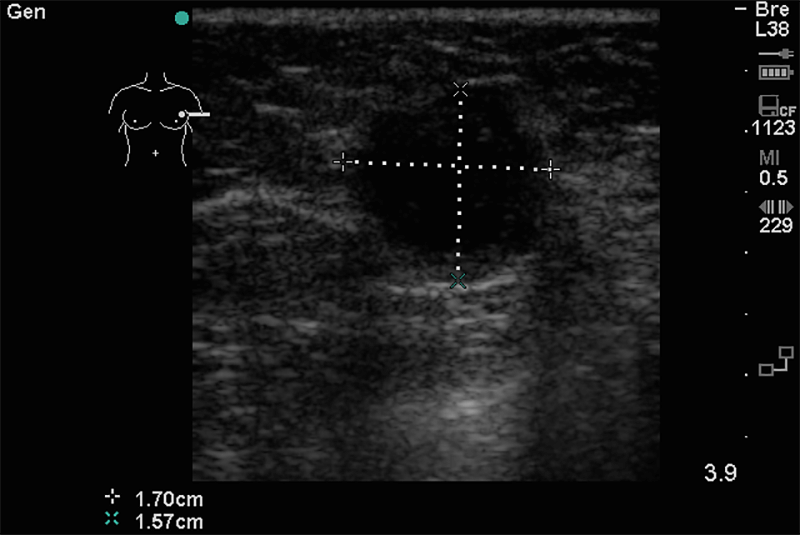

Tapintható emlőelváltozások esetén kimagasló jelentősége van az ultrahang vizsgálatnak. Eldönthető, hogy az adott elváltozás szerkezetileg milyen jellegû, folyadéktartalmú (cysta), avagy tömöttebb szerkezetû, mekkora, pontosan hol helyezkedik el, milyenek a kontúrjai. Ezek ismeretében nagy valószínûséggel megítélhető, hogy rossz- vagy jóindulatú elváltozásról van-e szó.

Az esetek egy részében az ultrahang kiválthatja a mammográfiát, más esetekben azzal kiegészítve teljes értékû. Negyven éves kor alatti hölgyek esetében szûrővizsgálatként is alkalmazható. Jóindulatú cysták kontrollálása is ultrahanggal történhet.